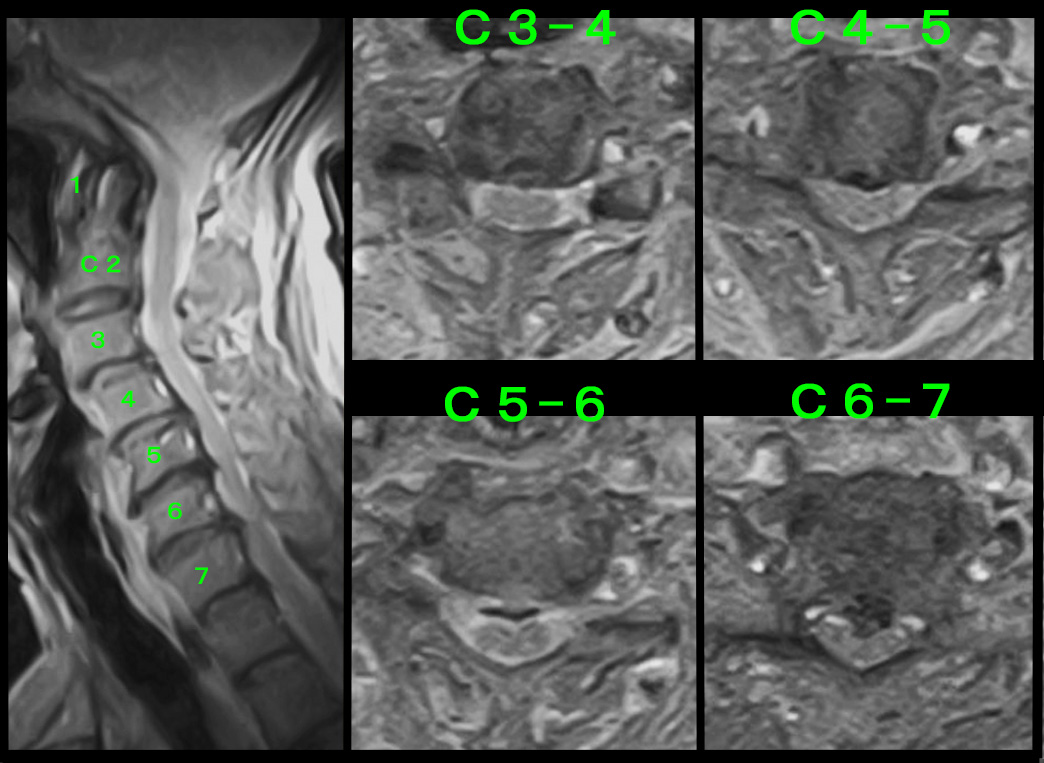

初診時の頚椎MRI検査では、C56とC67に椎間板ヘルニアが確認されました。

私は、C67の椎間板ヘルニアが新鮮なもの(最近発症または悪化したもの)と判断しました。